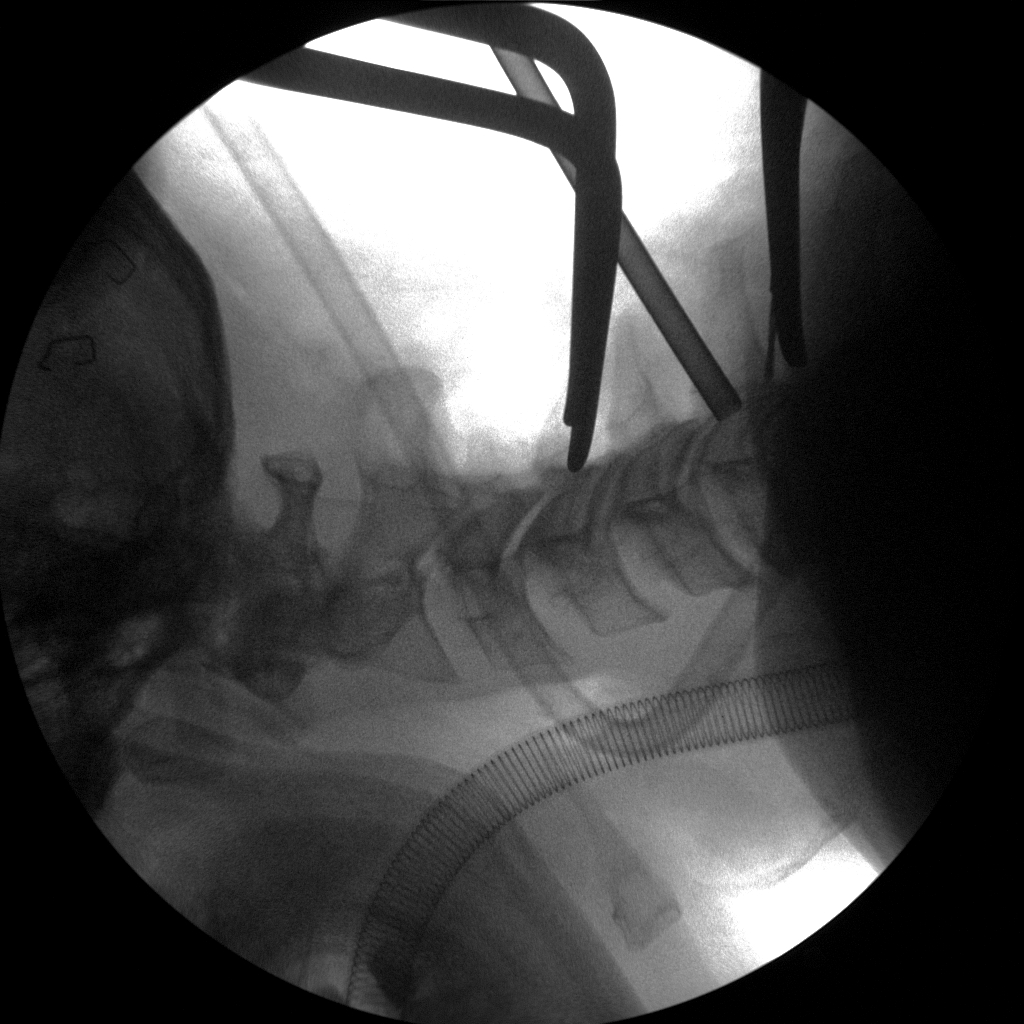

Anterior Cervical Discectomy & Fusion